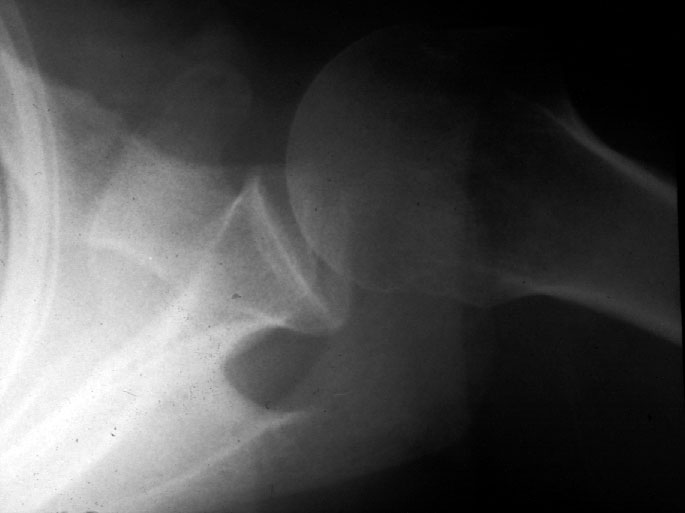

Normal Shoulder (axial) -- Identify: clavicle, acromion, corocoid process,

glenoid, humeral head